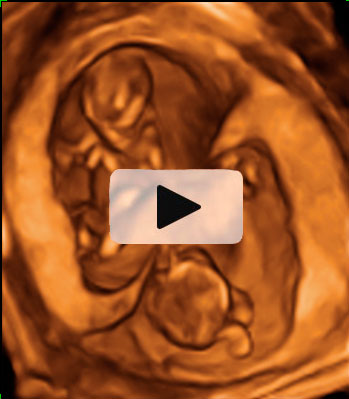

Ecografía Embarazo 2D y 3D - SEMANA 12